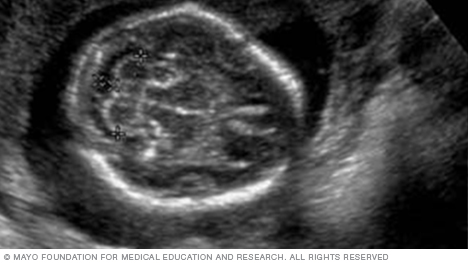

Below is a view of a fetus's head. The thicker white lines that form a circle are the skull. The white line in the middle of the circle is the midline structure that separates the baby's brain into its right and left halves. Head measurements can help determine the age of a fetus.